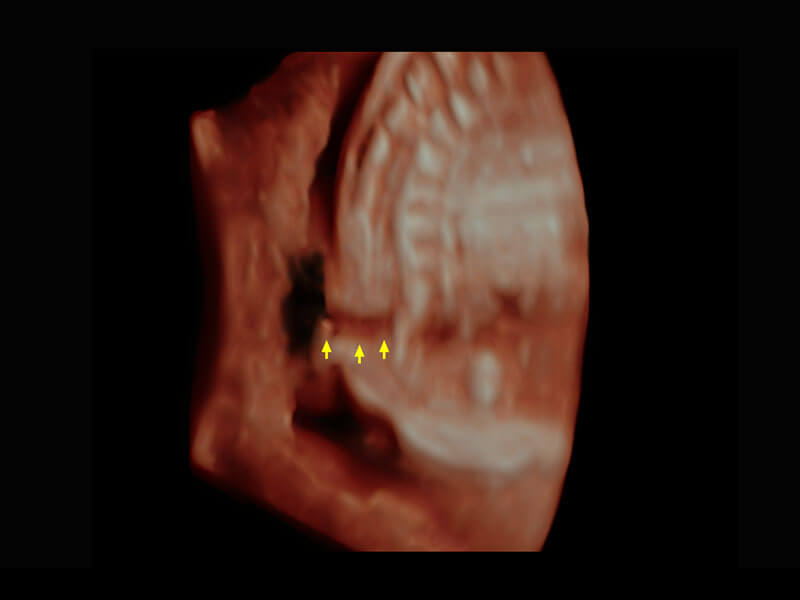

腔内三维-宫内节育器

腔内三维-光影成像